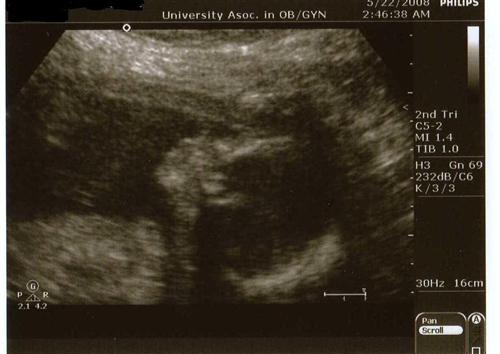

Baby Neener update w/PICS

We had the sonogram this afternoon, the technician was a little stale, obviously didn't realize how freaked out we were. She kept saying, "I'll tell you when I'm done." Yeah, so an HOUR later they got all the pictures they needed except one, the 4 chambers of the heart. So we have to go back in 2 weeks for that picture, and a growth sono.

We had 3 technicians trying to get this one shot. We are all now positive that our baby is stubborn as all get out as he/she kept squirming and moving from the time they put the wand on my stomach.

But the most important part is the baby is HEALTHY!!!!! They said that there is no evidence showing them that this baby has trisomy 18. Obviously doctors cannot be 100% sure about anything, but they said everything looked fine and the baby was healthy. Makes me so much more confident in my decision not to do the amnio (and having a needle so close to the baby), especially at the amount of movement this baby had, it was non-stop!

Here's the pictures I received: